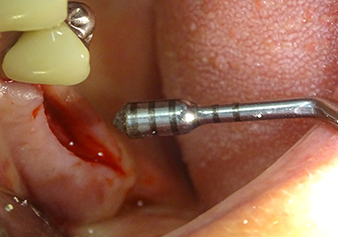

Following an intermediate check (Fig. 4) a further preparation step was performed (Fig. 5). Afterwards, the hydraulic Z35P instrument was used to lift the membrane to the desired position (Fig. 6 and 7). This was followed by further piezosurgical preparation of the implant bed, concluded with a rotary bur and shoulder milling cutter up to the implant diameter of 4.8 mm. Before the implant was inserted, the augmentation material (particle size approx. 0.8-1.6 mm) was introduced underneath the Schneiderian membrane (Fig. 8).